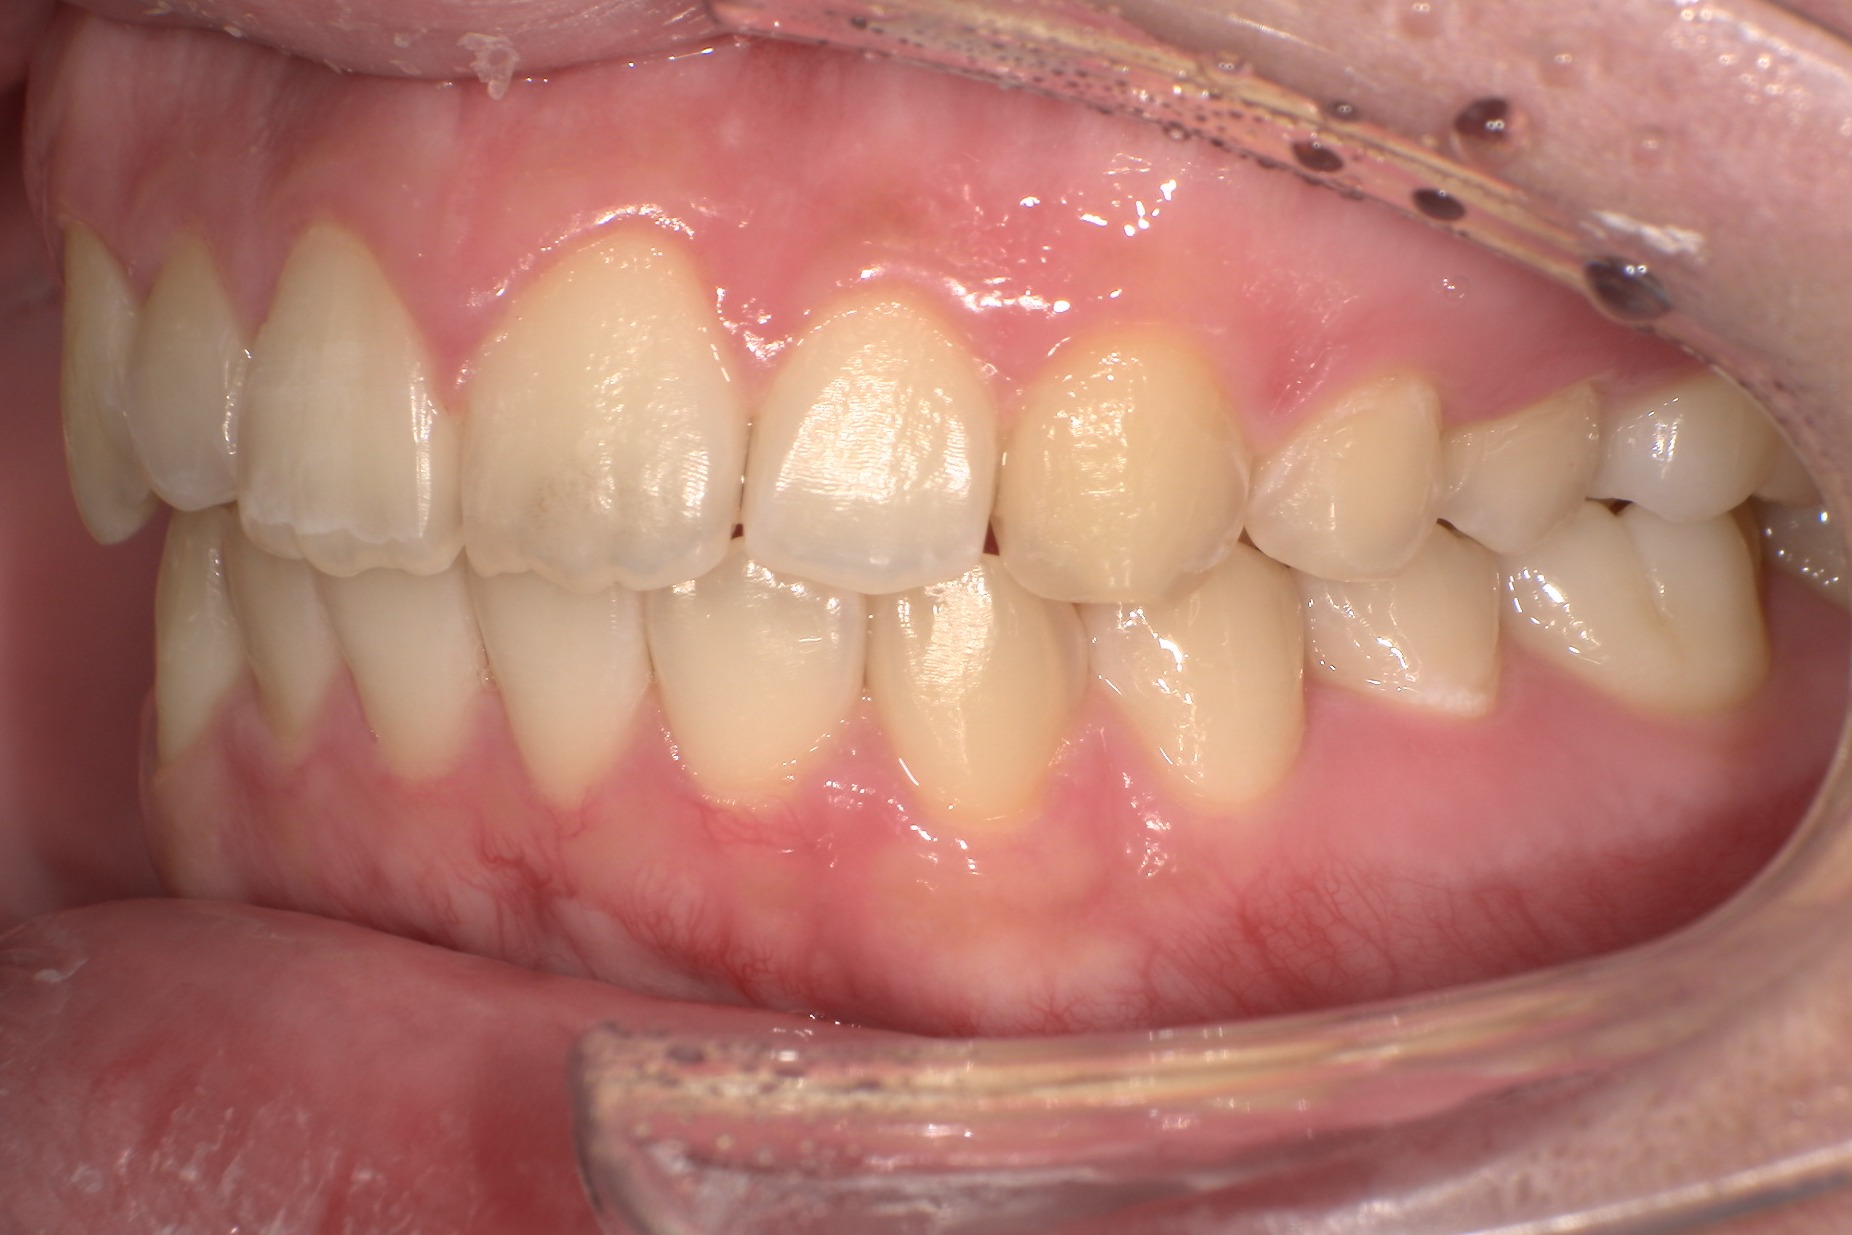

ここでは、インビザラインを使用して出っ歯を改善した実際の症例をご紹介します。それぞれの患者様が抱えていた悩みや治療の経過、治療後の変化を通して、インビザライン治療の効果やメリットを具体的に解説します。

医師の解説

今回の症例では、非抜歯によるインビザライン矯正を選択しました。叢生や強い上顎前突がありましたが、短期間で効率的な改善を達成しました。

| 詳細情報 | |

|---|---|

| 費用 | 360,000円(税込396,000円) |

| 治療期間 | 6ヶ月 |

| 治療内容 | マウスピースを用いた歯列矯正 |

| 追加処置 | IPR |